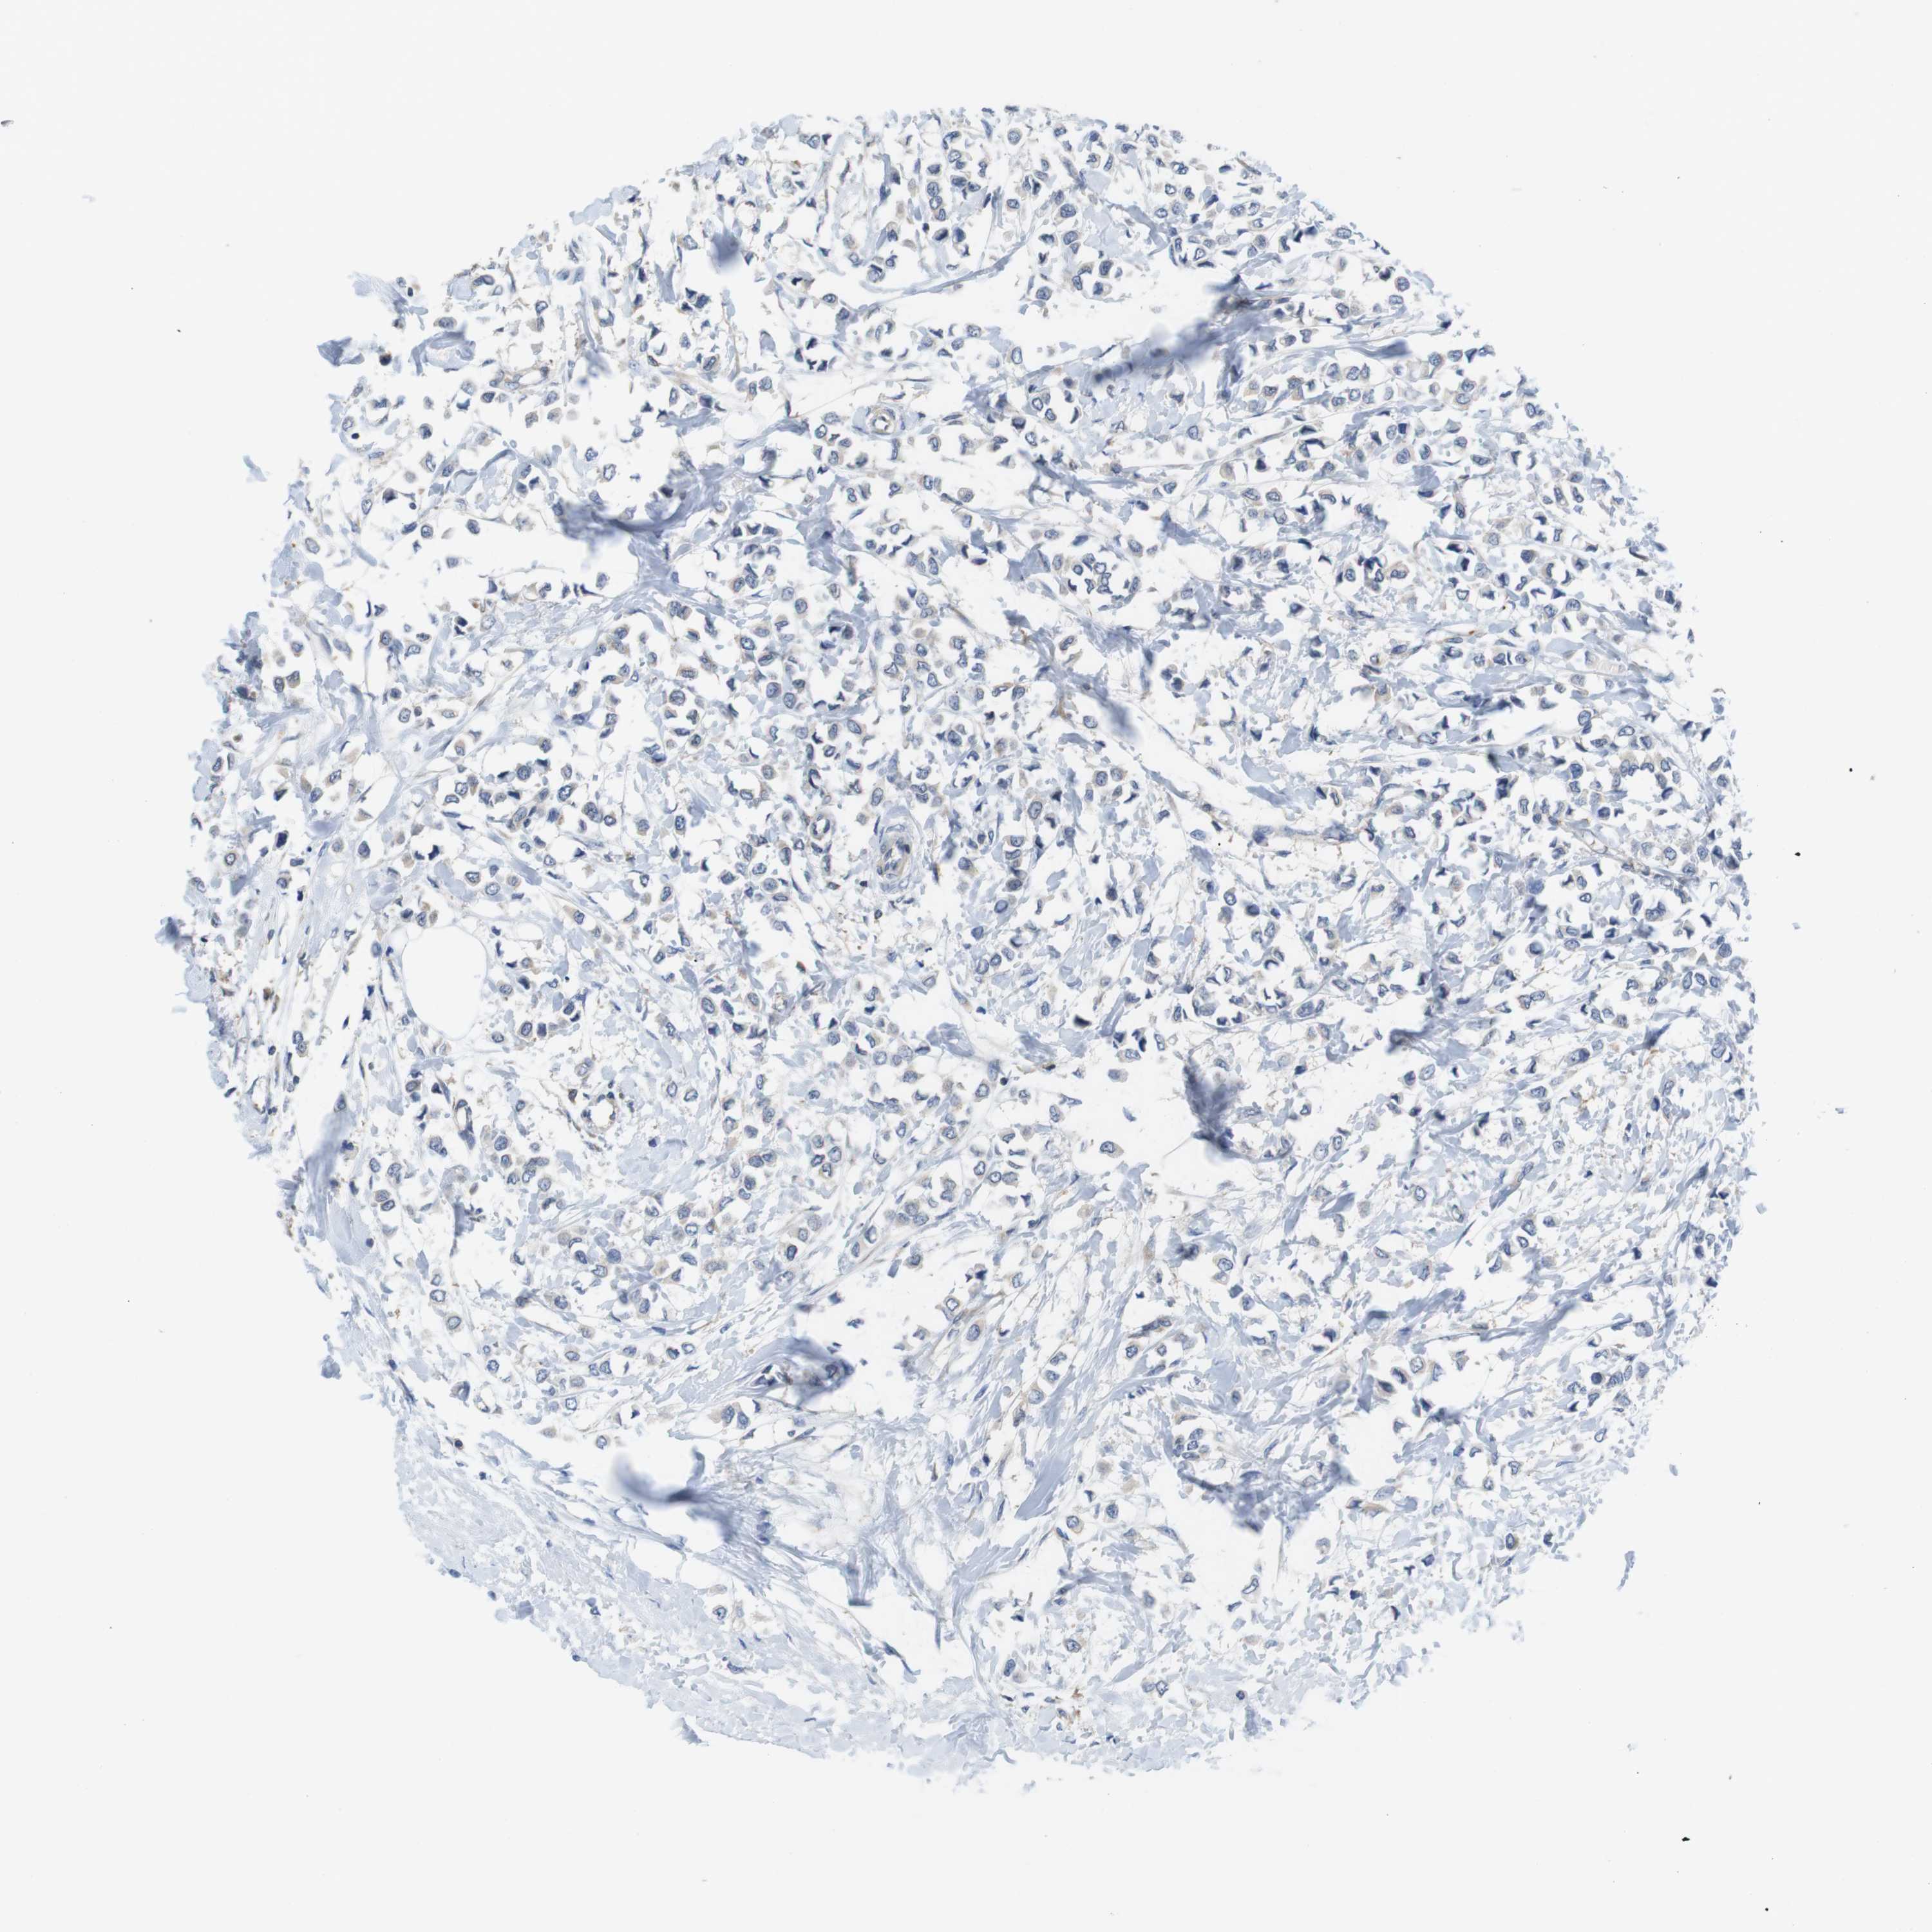

CANCER BREAST CANCER Show tissue menu

BRCA TCGA BRCA VALIDATION PROTEIN EXPRESSION